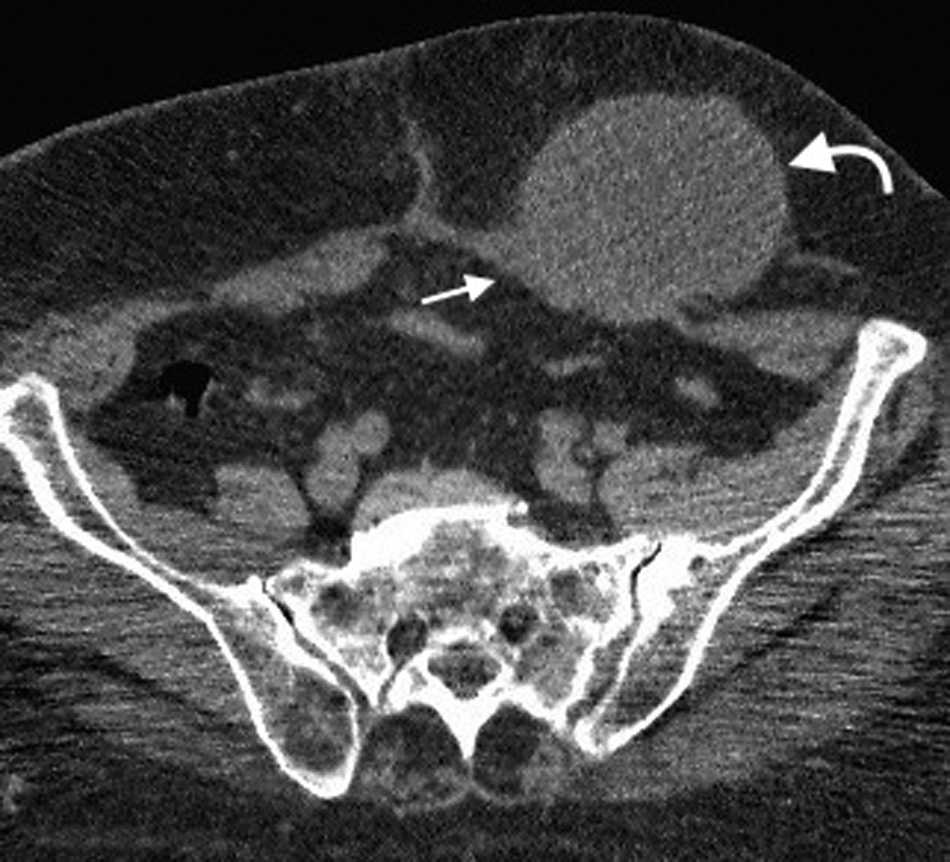

Su diagnástico clínico es difícil porque su incidencia es infrecuente, su localizaci??n profunda y tiene pocos signos o s??ntomas espec??ficos, como los relacionados con la compresi??n del nervio obturador (signo de Howship-Rombeng)10. El foramen obturador se conforma por la continuidad de los huesos isqui??ticos y p??bicos, y est?? cubierto por la membrana obturatriz, excepto en el receso anterosuperior donde es perforada por la arteria, la vena y el nervio obturador, que viajan a lo largo del t??nel de 2-3 cm formado por los m??sculos obturadores internos y externos. A trav??s de este defecto, se produce la hernia peritoneal11.

Es m??s com??n en mujeres mult??paras de edad avanzada debido a la debilidad generada en el piso p??lvico, aunque tambi??n se ve en pacientes con aumento de la presi??n abdominal y ancianos debilitados1.

Su diagn??stico espec??fico se puede hacer si en la TCMD de pelvis se visualiza el intestino herniado entre los m??sculos pect??neo y obturador externo con obstrucci??n del intestino delgado sin una causa aparente3 (fig. 4).